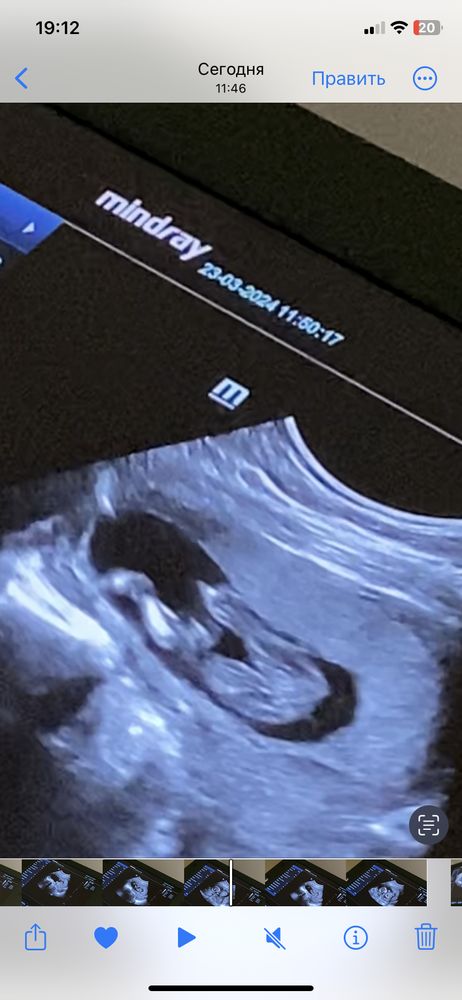

Где там мальчик?! Девочкино "кофейное зёрнышко", особенно на второй фотке.

Девочка же,какой мальчик))) кофейное зёрнышко вон торчит

Счастье Любит Тишину, на 2 или 3 фото? Я вот не понимаю о каком зернышке говорят)) 🙈 девочку хочу!) и врач прям удивила меня с тем, что мальчик😄 я спала и видела, что девчонка у меня

Дарья , на 2))